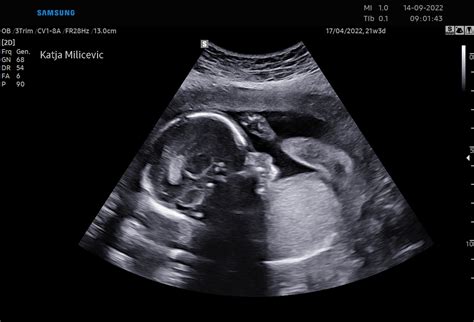

V 29. tednu nosečnosti otrok široko odpira oči, kar je mogoče opaziti tudi na ultrazvočnih posnetkih. Razvija se sposobnost uravnavanja telesne temperature, kostni mozeg pa je popolnoma dozorel in samostojno proizvaja vse rdeče krvničke brez pomoči jeter in vranice. Otrok v maternici tudi lula, s čimer proizvede do pol litra plodovnice dnevno.